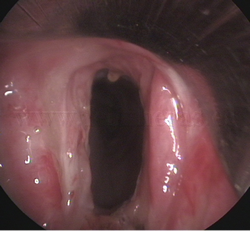

Patología

tráqueo-bronquial |

Cuerpo

extraño endobronquial |